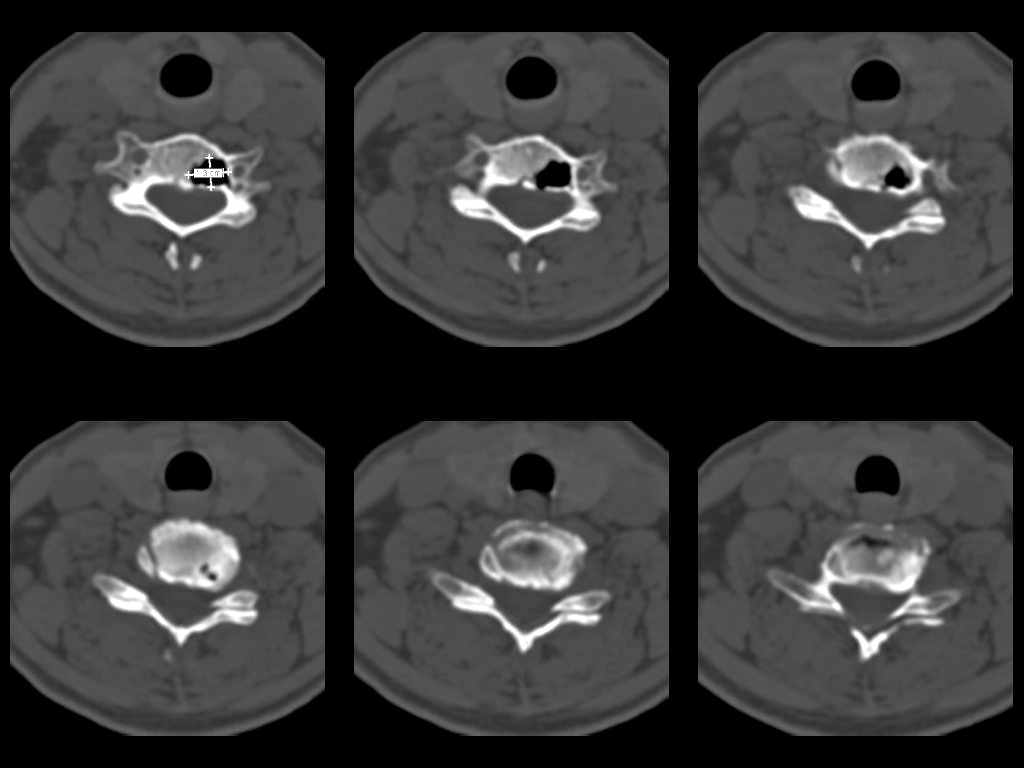

Участок деструкции в теле позвонка. |

У женщины 49 лет, при рентгенографии шейного отдела в теле С6 выявлен участок деструкции.Часть N1 Больная находилась в неврологическом отделении с диагнозом энцефалопатия. Была проведена КТ тела С6, 26.12.2002 выявлен участок деструкции 0,9х1,2 см, плотность участка составляет -1022 ед.Н. аналогичная плотности воздуха в трахее.Возникает вопрос что это? Метастаз, киста,или какой то вредный анаэроб грызет тело позвонка?Через пол года 03.06.2003 произведено повторное исследование. Отмечается отрицательная динамика. Участок деструкции увеличился в размерах, увеличелась площадь разрушения задней поверхности тела С6.

Наличие выраженных дистрофических изменений, а также сообщение полости в теле позвонка С6 с полостью межпозвонкового диска в сегменте С5-С6, а также наличие газа в полости межпозвонкового диска С5-С6 спереди, на границе фиброзного кольца и пульпозного ядра (3-й слева срез в нижнем ряду на второй из представленных КТ) делает диагноз остеохондроза, осложненного вакуум-феноменом и прорывом газа в полость тела позвонка с формированием воздушной кисты (пневмкисты) несомненным.

Размеры за 2002 год 1,2х0,9х1,2 мм

за 2003 1,3х0,9х1,2 мм. Но контур деструкции стал более неровный и внедрение в дужку С6 увеличелось.

Характер процесса не вполне ясен. Учитывая скопление газа на фоне тела

позвонка, с наибольшей вероятностью - "вакуум-феномен" в следствии

дегенерации межпозвонкового диска. Наложение газа на образование в теле

позвонка (гемангиома?) создает затруднение в диагностике (по-видимому

сочетание двух процессов). Желательно МРТ исследование. Если возможно,